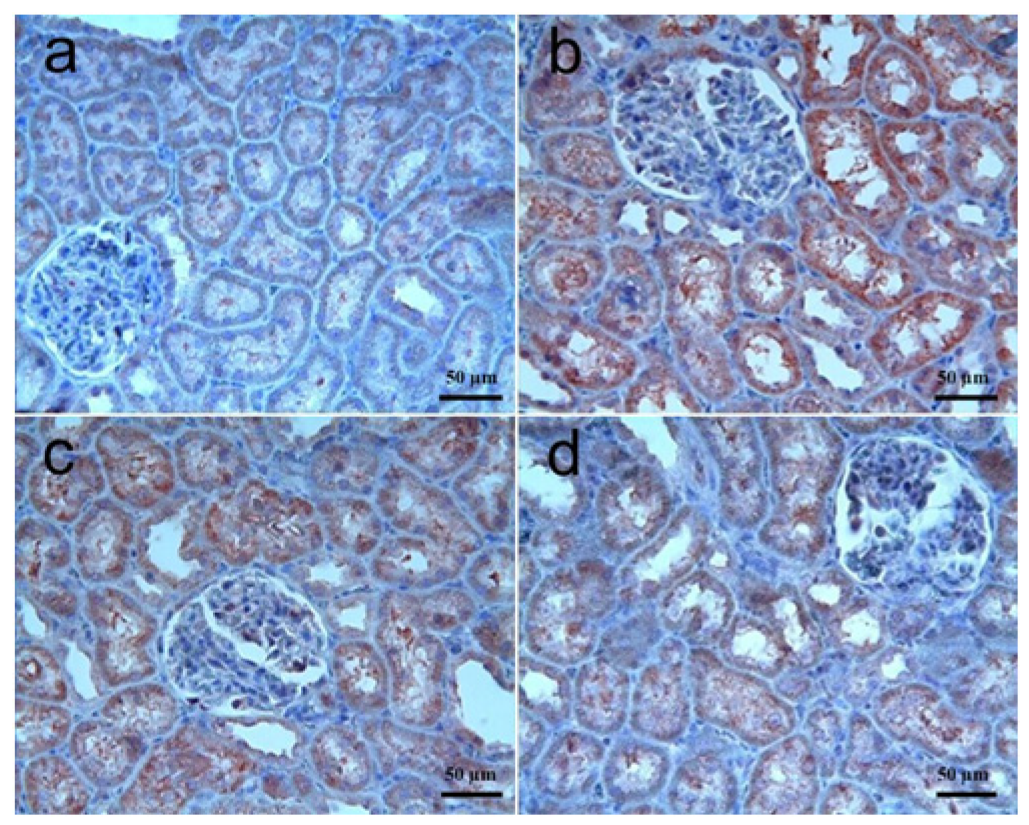

3.3.1. Kidney Tissue

| VEGF immunoreactivity | 1 (0–2) | 0 (0–1) c | 1 (0–2) d | 1 (0–2) d |

| FGF immunoreactivity | 1 (0–2) | 0 (0–1) c | 0 (0–1) | 0 (0–1) |